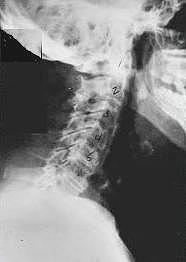

Phase One - Subluxation Degeneration

Subluxation Degeneration - Phase One Phase One Subluxation Degeneration is seen in subluxations that have been present for up to twenty years. This phase is characterized with a loss or change in the normal curve in the spine. On this example you can see that the normal forward (lordotic) curve is lost. This spine even has developed a reverse curve in the neck. The disc spaces have also begun to exhibit a slight change in shape. One good point is that the bodies of each of the vertebrae (the square part in front) still exhibits clean clear borders. Segmental motion may be abnormal but overall motion is probably not affected. Chiropractic reconstructive care for a phase one can take from 6 to 18 months. More than 80% of people with Phase One Subluxation Degeneration have no pain. Therefore, if left uncorrected, phase one continues to progress with time until it eventually reaches the next phase.